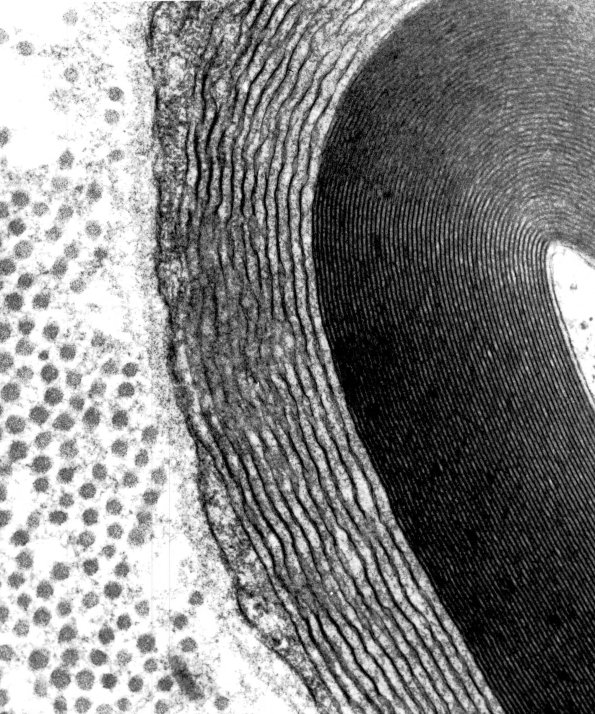

Higher magnification of image #3A1. (electron micrograph)